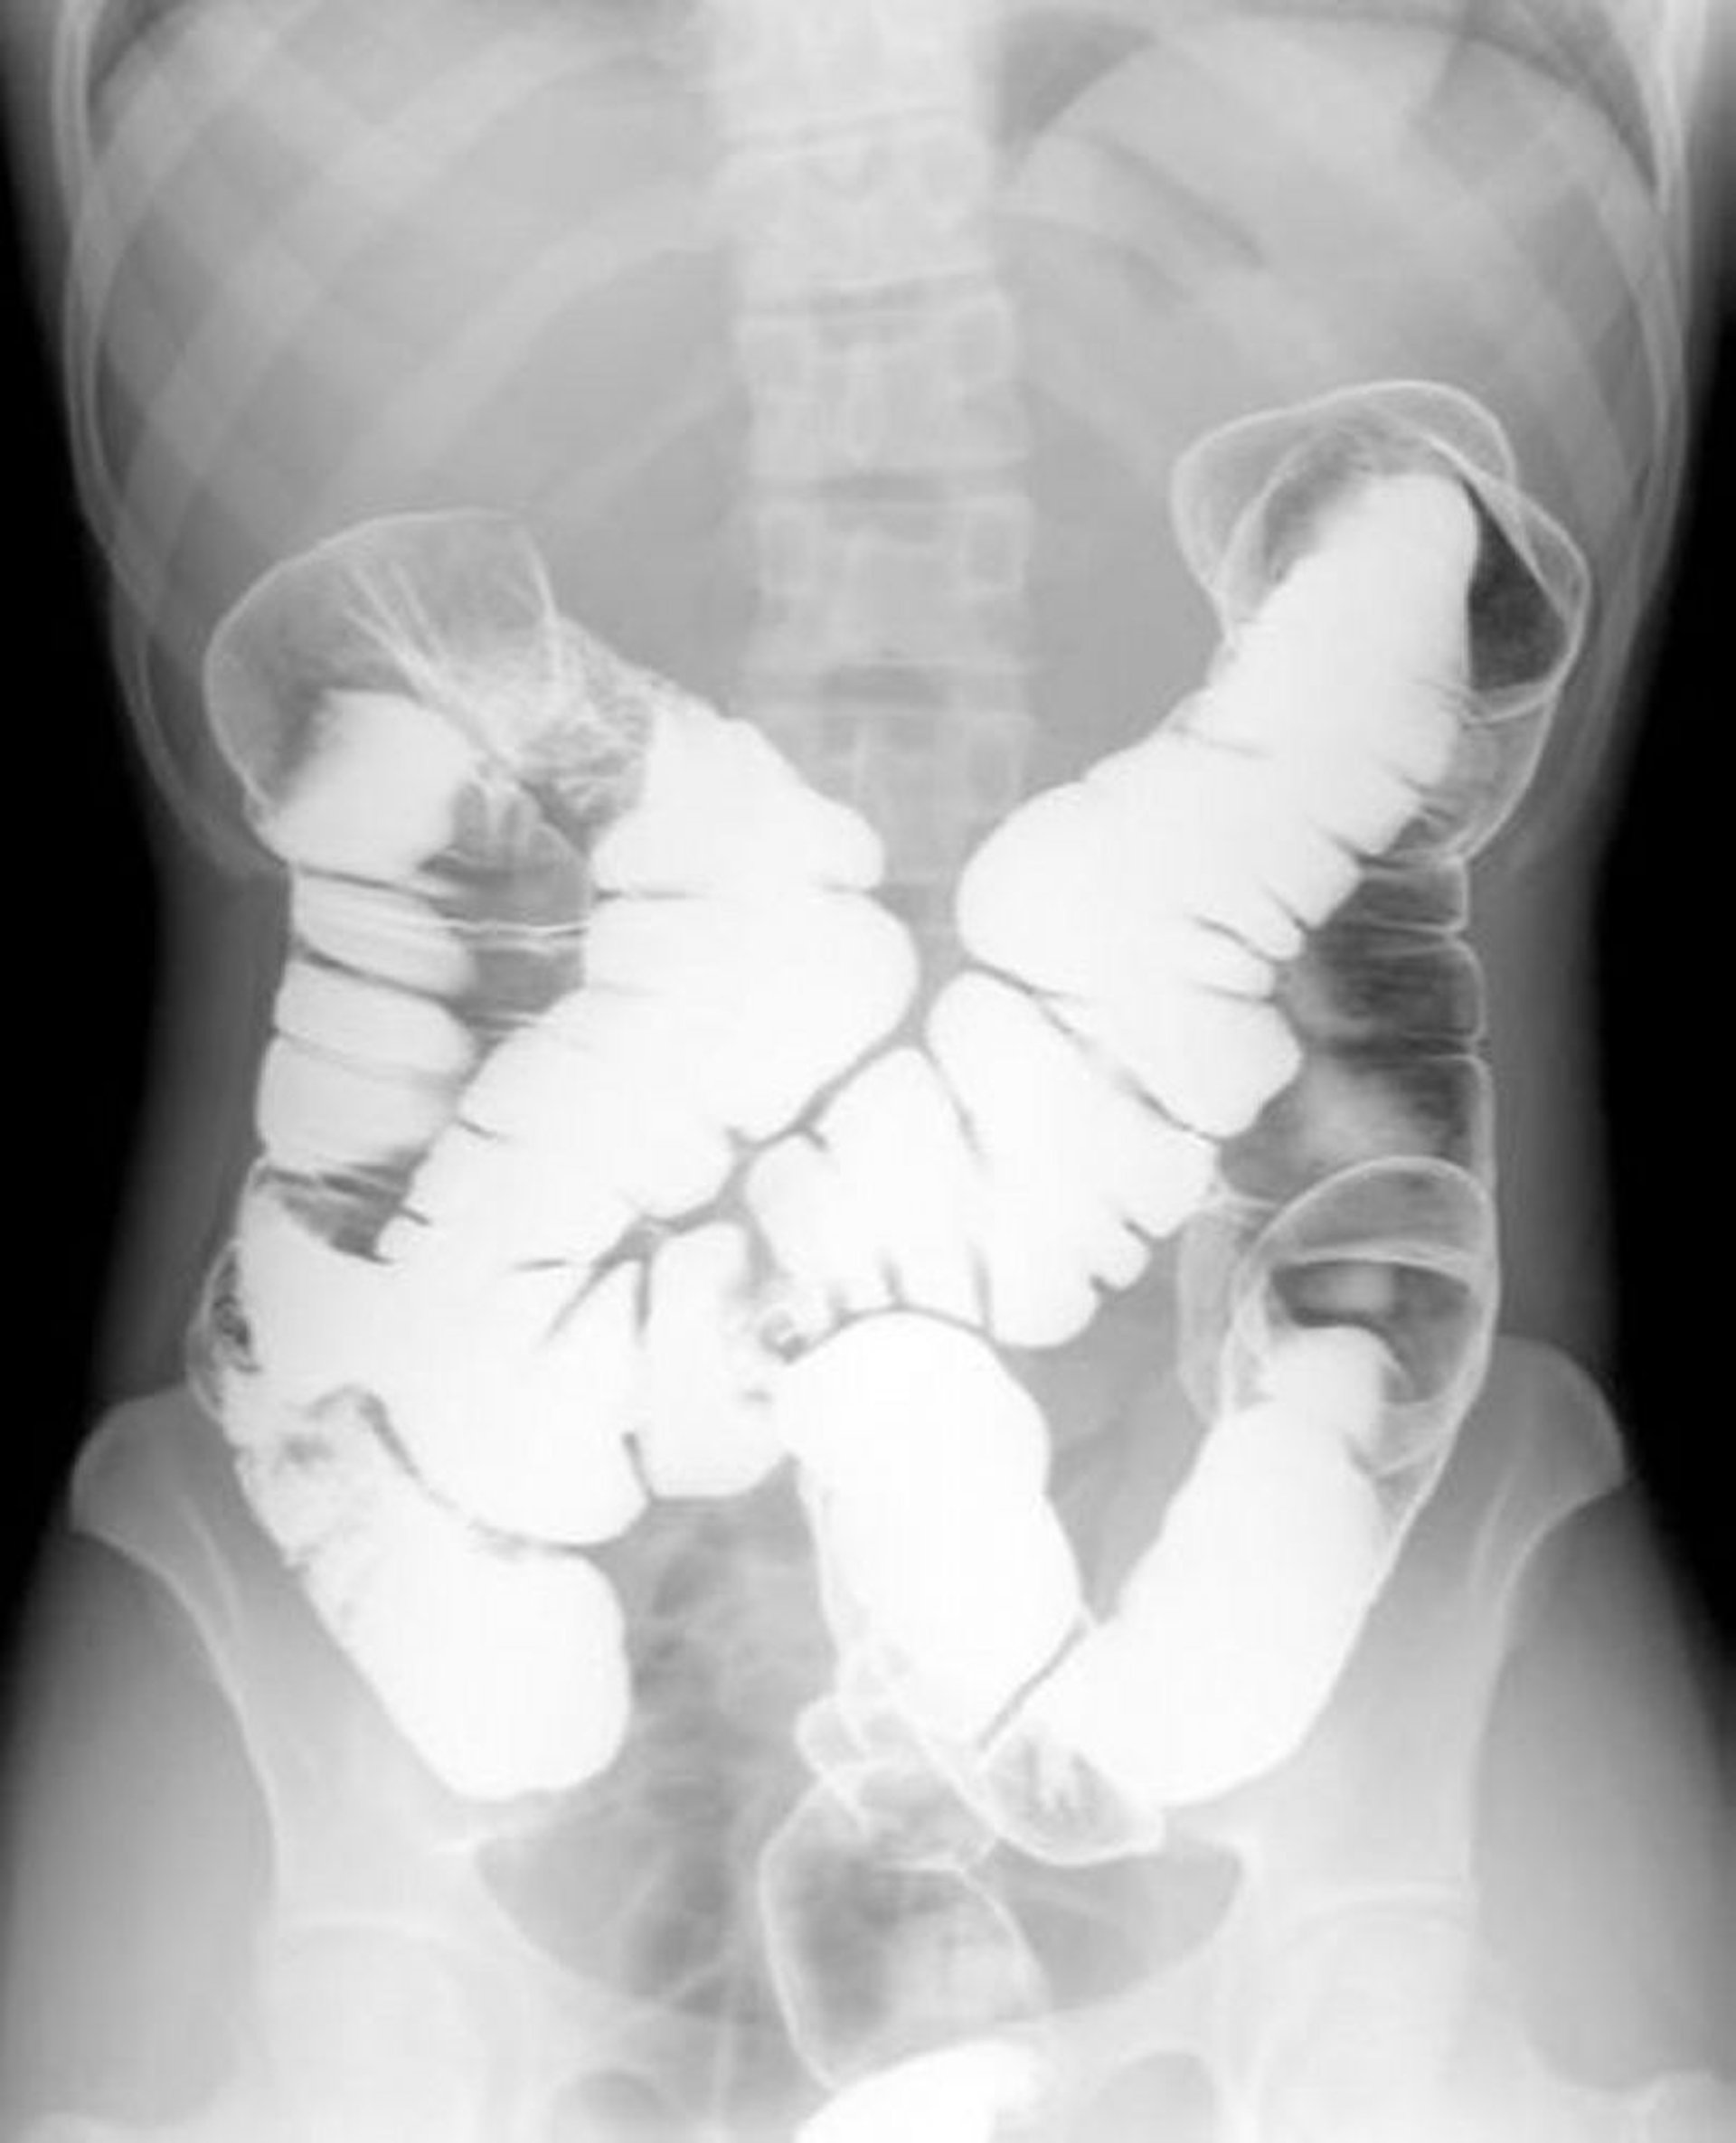

Enema baritado com duplo contraste mostrando anatomia normal

Essa imagem mostra o padrão de ar e bário no interior de um colo intestinal normal.